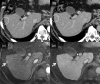

MRI is widely used in clinical practice for detecting liver diseases. Since the introduction of gadoxetic acid, MRI has become the most effective modality for the detection and characterization of focal liver lesions. According to previous meta-analyses, the area under the receiver operating characteristic curve (AUROC) was 0.97-0.99 for the diagnosis of small hepatocellular carcinoma (≥ 2 cm) by gadoxetic-acid-enhanced MRI. Moreover, the AUROC for the diagnosis of colorectal liver metastases was significantly high (0.98). Despite gadoxetic acid's drawbacks, its clinical utility outweighs them, making it the contrast agent of choice in routine liver MRIs. Moreover, clinically, liver MRI has become more prevalent for a quantitative assessment. Liver fibrosis can be evaluated using MR elastography; whereas, hepatic steatosis and iron overload can be evaluated using proton density fat fraction, with high accuracy and reproducibility. This article reviewed the usefulness of liver MRI, which can be a comprehensive imaging modality in clinical practice.